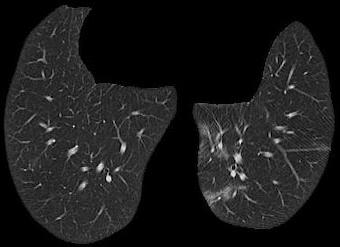

Figure 3 illustrates this further. It presents three cases of unsegmented slices of a CT scan (left column), along with their cases when they are segmented with conventional approaches (middle column) and with our proposed framework SAM2CLIP2SAM (right column). It is evident that the segmentation result with our approach is more accurate and error-prune. In the first case (top row), the mediastinal mass between the left and right lungs is kept when the slices are segmented with conventional approaches, whereas it is not kept (i.e., it is black) when the slices are segmented with our SAM2CLIP2SAM framework. In all cases, one can also note that a bit of the pleural space (e.g. on the peripheral of the lungs) is also kept and is not masked when the slices are segmented with conventional approaches; this is not the case when the slices are segmented with our SAM2CLIP2SAM framework.

Original-Unsegmented Conventionally segmented SAM2CLIP2SAM segmented